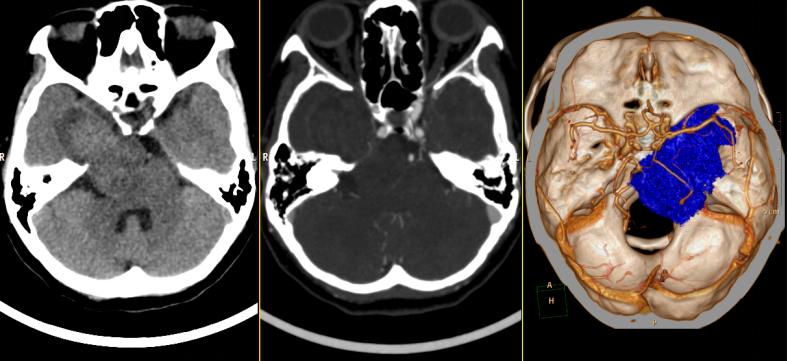

根据患者的症状描述与影像资料,与脑膜瘤、听神经瘤等鉴别诊断后,我院神经外六科主任吴杰考虑患者是右侧跨颅中窝、颅后窝肿瘤(三叉神经鞘瘤)。

▲术前检查

虽然基本确诊为三叉神经鞘瘤,但治疗却不易。患者的肿瘤较大,周围血供丰富,已经侵犯三叉神经,同时压迫邻近颈内动脉、右侧大脑中后动脉主干。吴杰介绍,“患者的肿瘤骑跨颅中、颅后窝,手术切除难度高。”颅后窝空间狭小,分布各种颅神经,稍有不慎将伤及周围神经或脑干,一次性全切手术难度系数和面临的风险巨大。

经过多次讨论分析,吴杰团队最终决定采用颞下入路,实施右侧岩斜区跨中后颅窝占位性病变切除术。术中可见质地硬韧的黄褐色肿瘤侵犯海绵窦、压迫脑干。吴杰小心翼翼分离肿瘤与周围神经,在显微镜下全切肿瘤,未伤及周围血管神经!